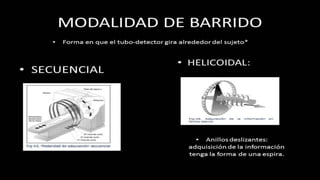

El documento define los conceptos básicos de pixeles, voxels y principios de calidad de imagen en tomografía computarizada. Explica que los pixeles son unidades de información en una imagen y los voxels son unidades de volumen que representan pixeles en secciones de corte. También describe factores como resolución espacial, de contraste y temporal que afectan la calidad de imagen, así como posibles artefactos.